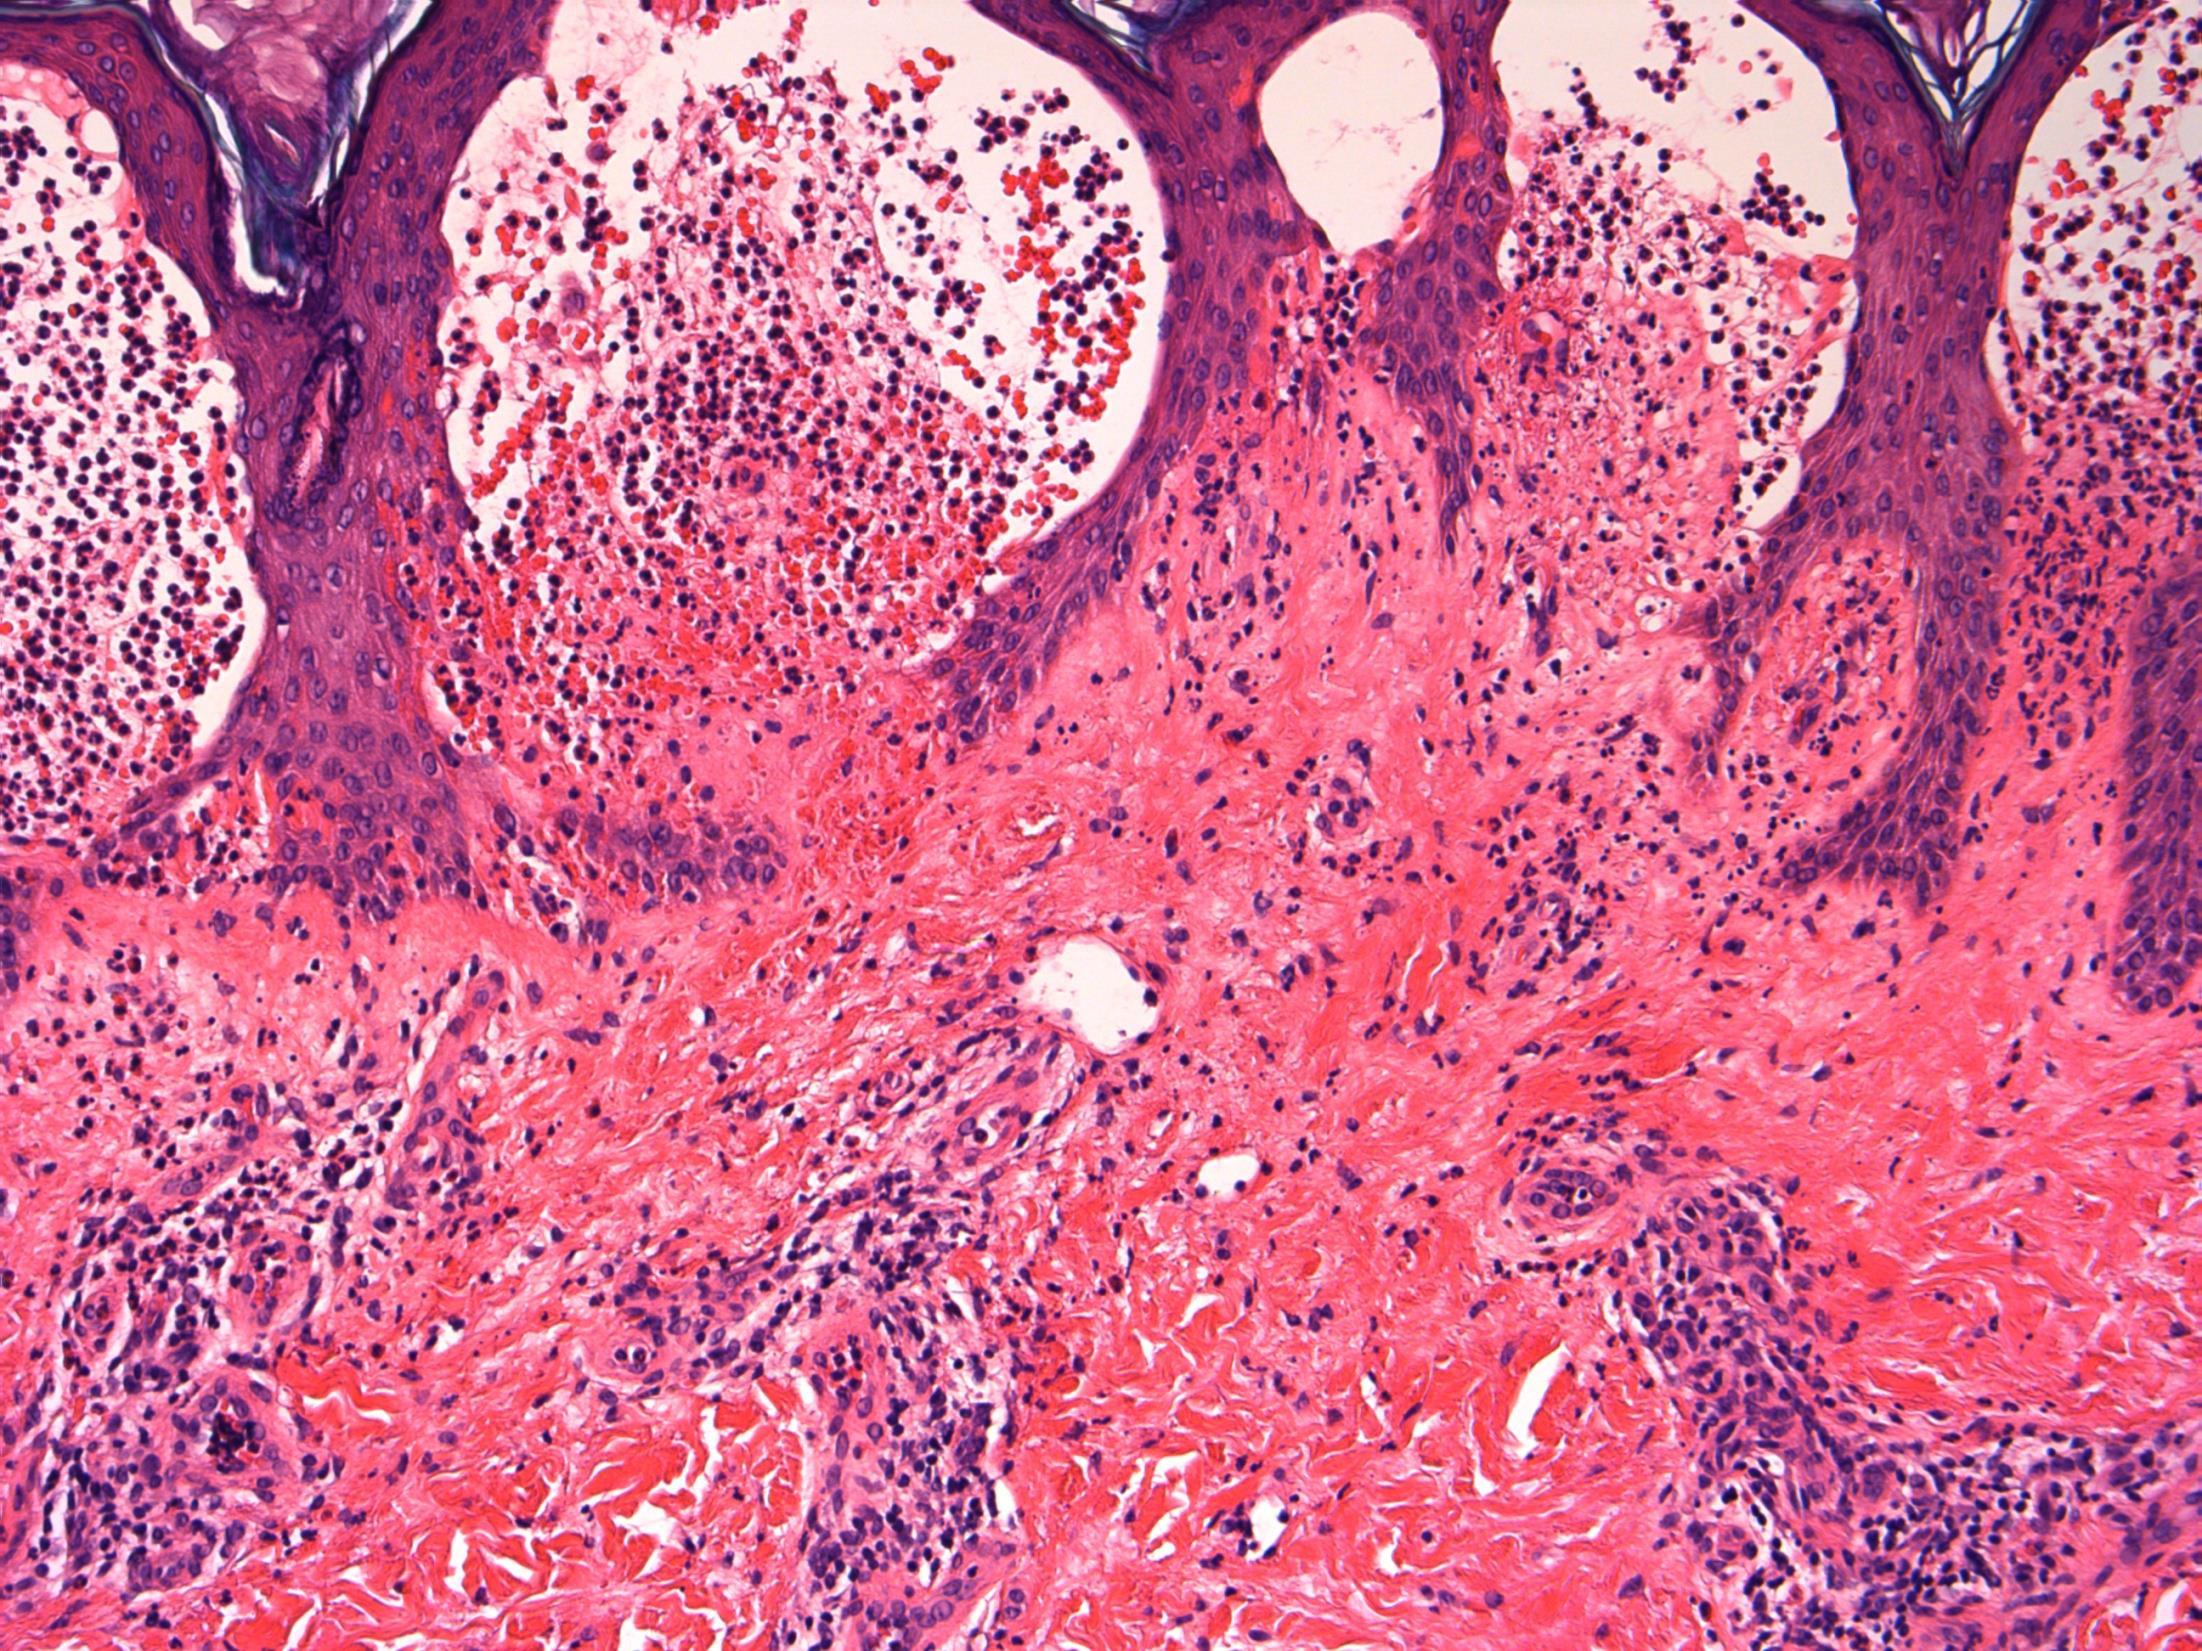

62F, with asthma, recently discharged from hospital after treatment for severe pneumonia. Now has sudden onset bloody diarrhoea and abdominal pain. Biopsy from sigmoid colon.

• Colon – Pseudomembranous coliltis

• Description: Patchy necrosis of mucosa, with mushroom shaped fibrinopurulent exudates on surface, crypt withering, hyalinisation of lamina propria

• Diagnosis: Pseudomembranous colitis

Differential diagnosis: Acute ischaemic colitis (can be very difficult – a lot depends on the history and clinical context, but usually more localised / segmental and full thickness necrosis)

• Plan: Correlate with microbiology, antibiotic history, endoscopy etc

• Comments: PMC typically follows antibiotic administration, which correlates well with the history provided. Caused due to toxins of C. difficile